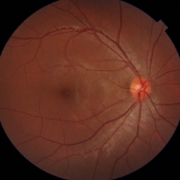

- 緑内障専門医が3名在籍。手術を含め的確な診断治療にあたります。

当院には3台の自動視野計がありますので、即日の検査が可能です。

緑内障に対する選択的繊維柱帯レーザー形成術を導入し、1年間に47眼に施行しました。4眼は無効、4眼は目薬を減らすことができ、36眼は3mmHg以上の眼圧の低下をみることができました。

副作用はほとんどありません。点眼薬で悩んでいらっしゃる方、ご相談ください。